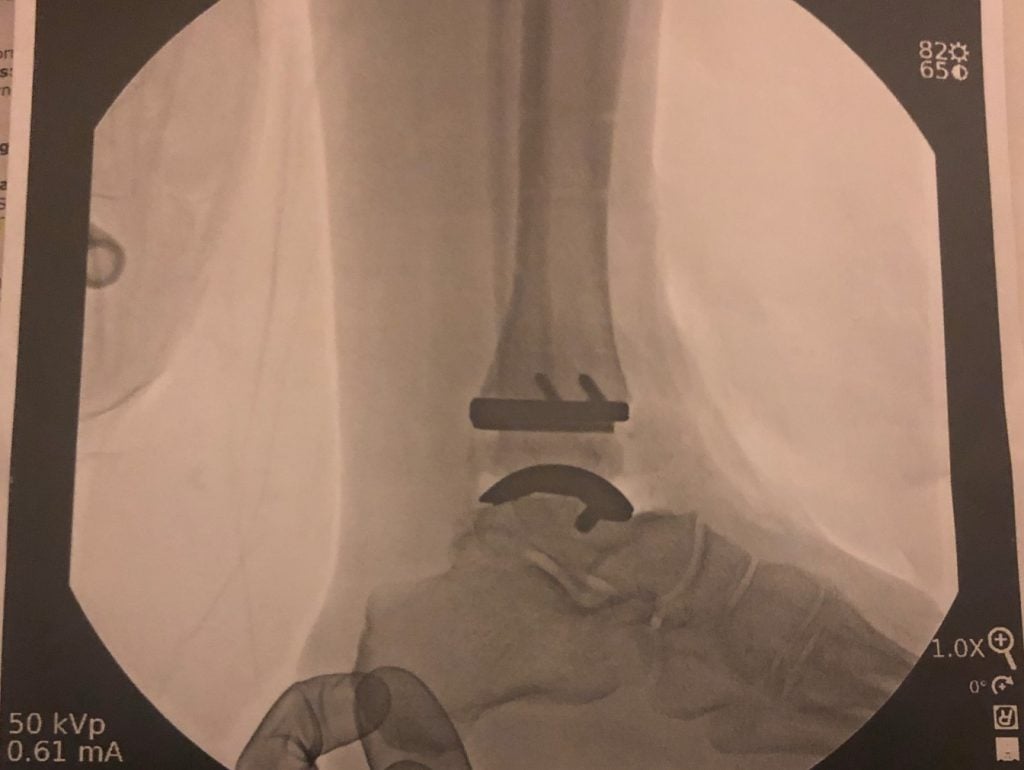

Ankle Replacement (Ankle Arthroplasty)

I’m a golfer with bone-on-bone arthritis in my right ankle. I tried braces and cortisone but nothing worked. It got so bad that I gave up playing golf. I went to three doctors - the first two wanted to do a fusion. Friends recommended HSS Stamford and Dr. Elizabeth Cody and I’m thankful they did. Dr. Cody reviewed my options as well as the pros and cons to both an ankle fusion and ankle replacement surgery. We decided that an ankle replacement was best for me. Dr. Cody explained surgery and what to expect post-surgery. Everything she said came true. I’m back playing golf and gardening without pain. I recommend HSS and especially Dr. Cody for ankle replacement surgery.